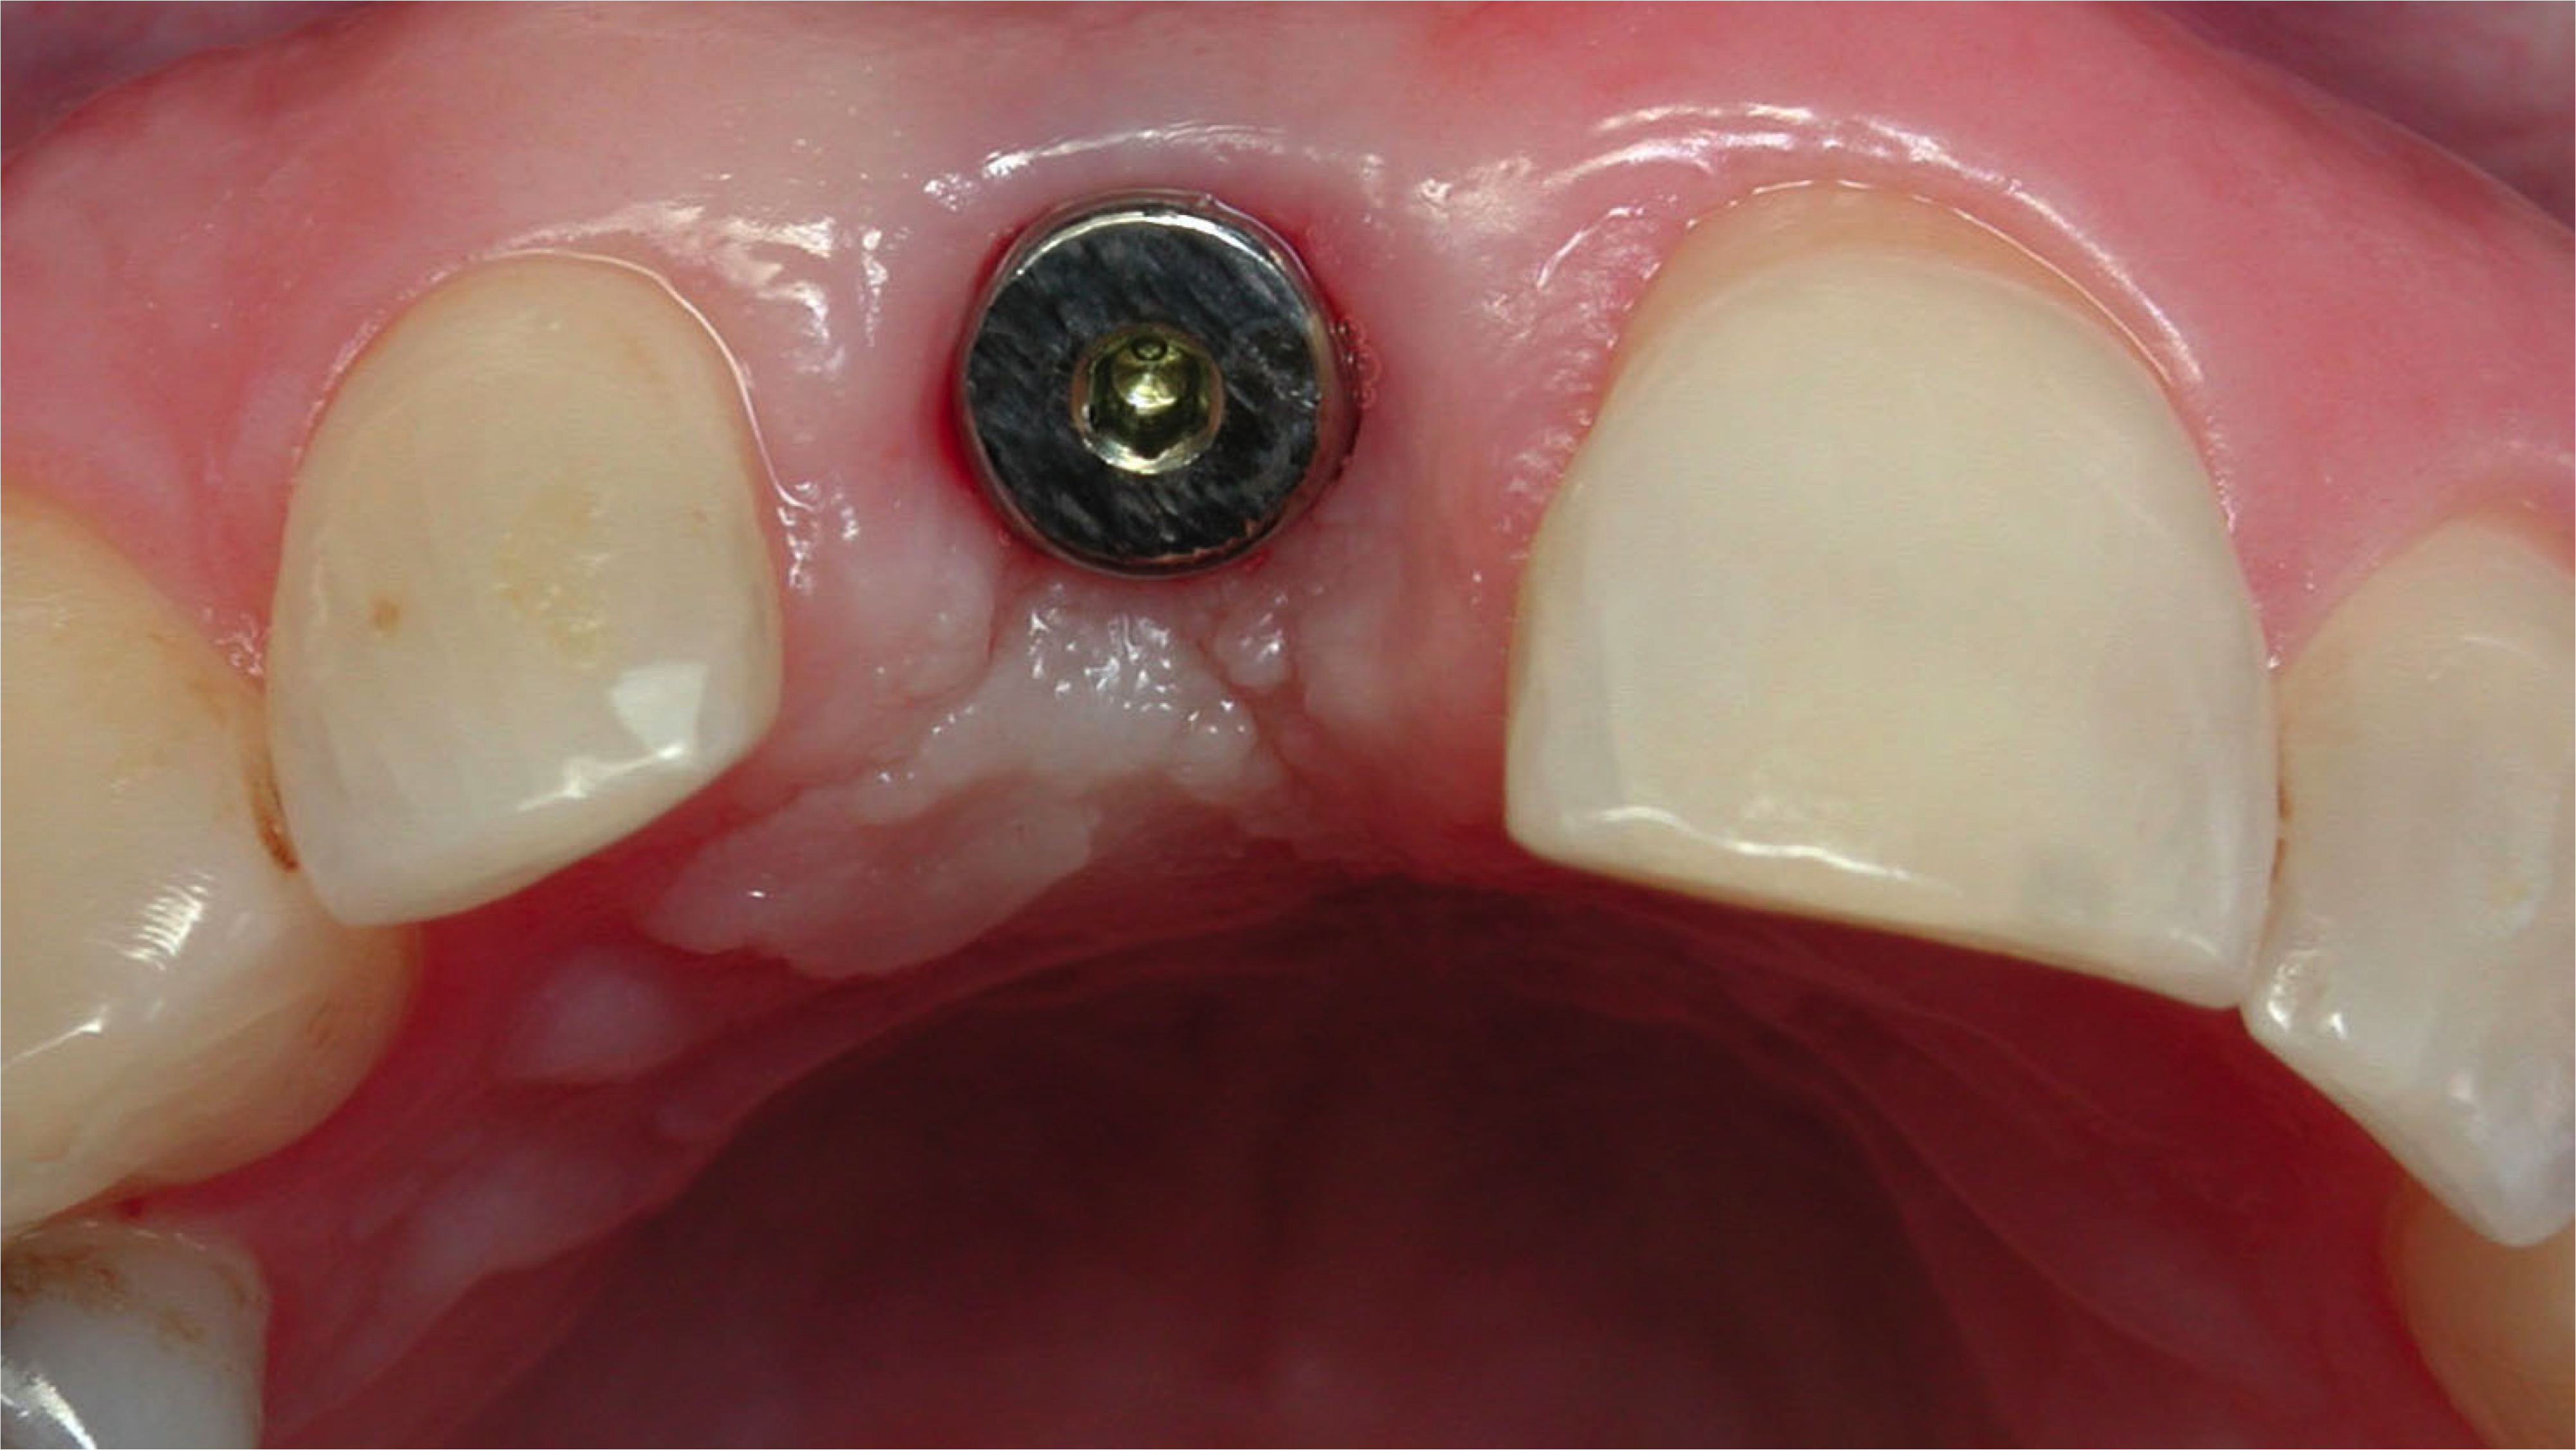

Fig 1. A female patient presented missing tooth No. 8, which would be replaced with a single implant restoration.

Figure 1

Fig 2. The ridge was of adequate size and dimension, so a 4.3-mm implant was selected.

Figure 2

An example illustrating the manner in which these factors are considered in case selection, implant placement, and implant restoration is the case of a female patient who presented with a missing central incisor, tooth No. 8 (Figure 1 and Figure 2). While this example presents an ideal situation for a single implant-supported restoration, analysis is required to determine the appropriate implant width and length, presence of adequate bone, quality and quantity, soft-tissue health, abutment type (ie, custom or stock), and restoration type (ie, cement- or screw-retained).